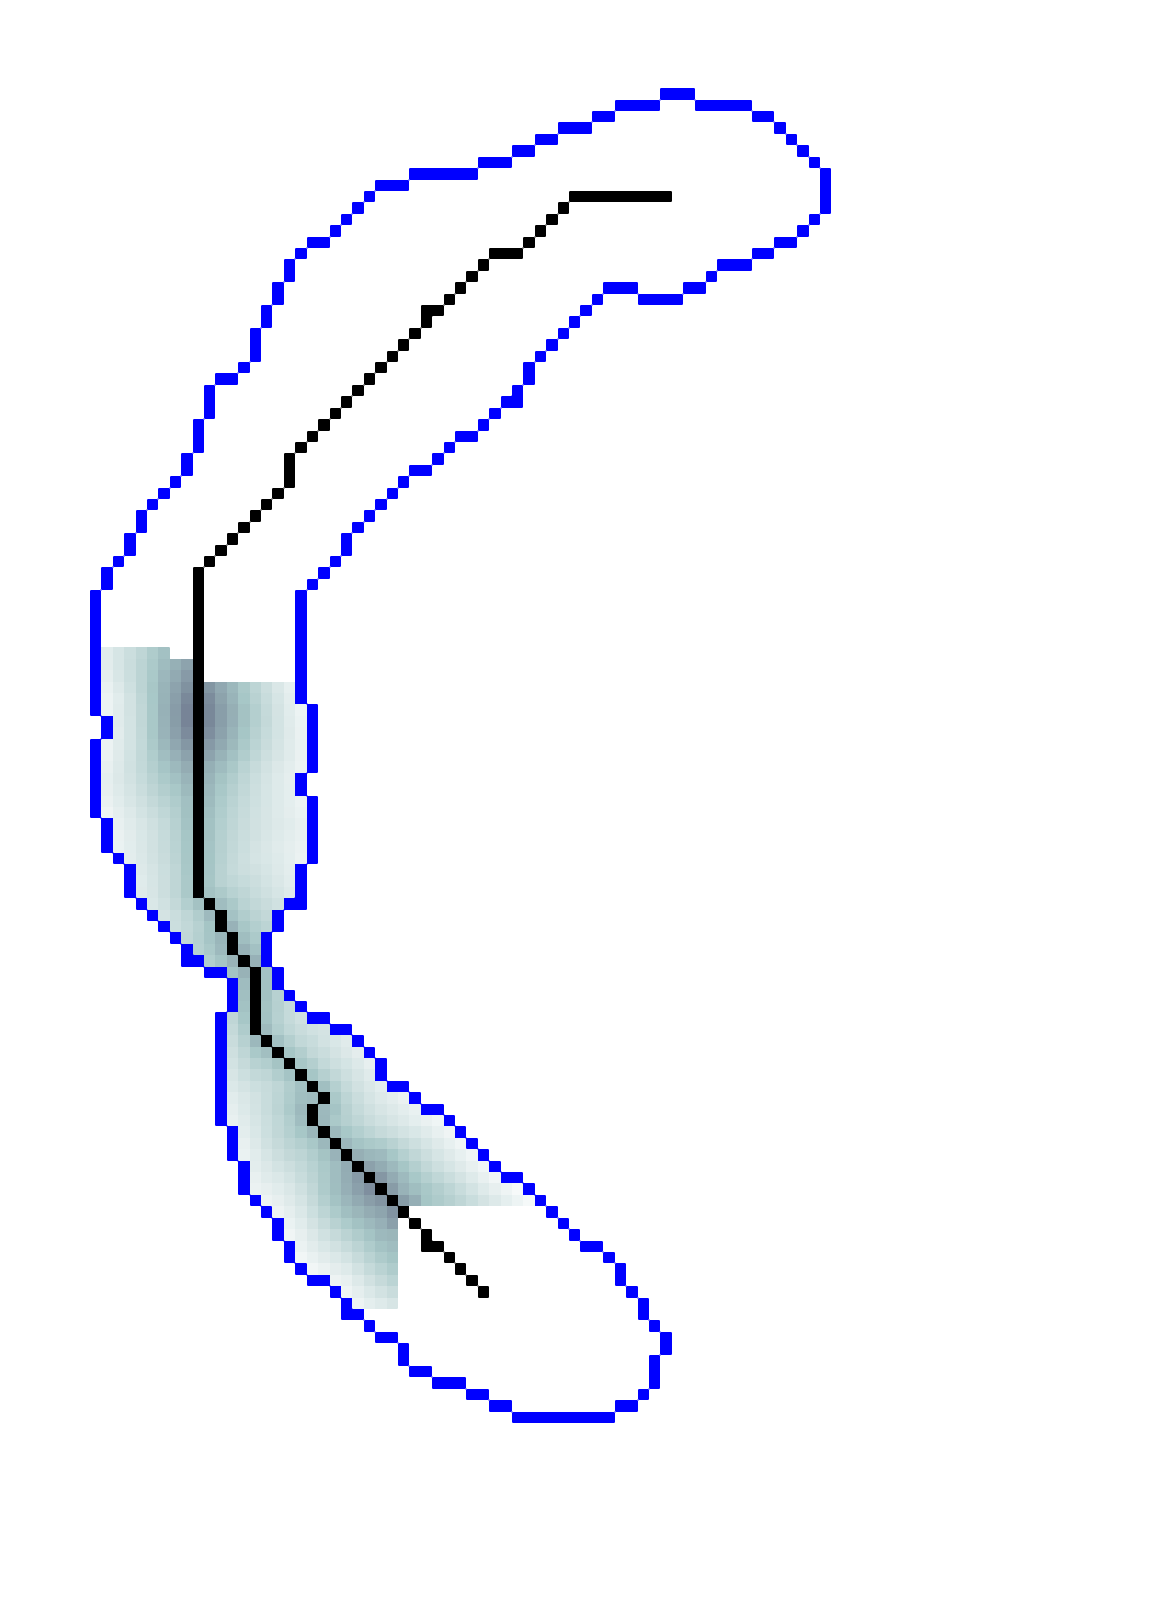

Geodesic paths are determined by back-tracing when different regions collide. The connecting geodesic is extracted minimizing at the collision grid-points. The aFM maps, i.e. ; the Voronoi index map , representing the label associated to each propagating seed; and the Tag , representing the state of each grid-point (Front, Visited, Far), are then updated within the collided regions, so that these merge as one and the front is consistent with the unified resulting region. This is continued until all regions merge.

Initialization. The seeds are aligned towards the vessels’ mid-line with a constrained gradient descent, resulting in an initial set of sources . All 26-connected components initialize the aFM maps, i.e., , , , and constitute also the initial geodesics .

Fast Marching Step. The aFM maps are updated by following an informative propagation scheme. We refer to [4] for the 3D aFM step considering the 48 simplexes in the 26-neighbourhood of the Front grid-point with minimal .

Path Extraction. Collision is detected when Visited grid-points of different regions are adjacent. A connecting is determined by linking the back-traced minimal paths from the collision grid-points to their respective sources with a gradient descent on (fig. 2). The associated integral geodesic length is computed and the connectivity in is updated in the form of an adjacency list. Lastly, the grid-points of the extracted are further considered as path seeds in the updating scheme, since furcations can occur at any level of the connecting minimal paths.

Fast Updating Scheme. A nested aFM is run only in the union of the collided regions using a temporary independent layer of aFM maps, where , , and . Ideally, the nested aFM is run until complete domain exploration, however, to speed up the process, the propagation domain is divided into the solved and unsolved sub-regions, and the update is focused on the latter (fig. 2). The boundary geodesic values of equal the geodesic distances at the collision grid-points. Lastly, the aFM maps are updated as: , , and .

| Initialization | FM Steps | Collision, Path Extraction and Update | Convergence | ||||||

| Descent | … | Stop Criterion | |||||||